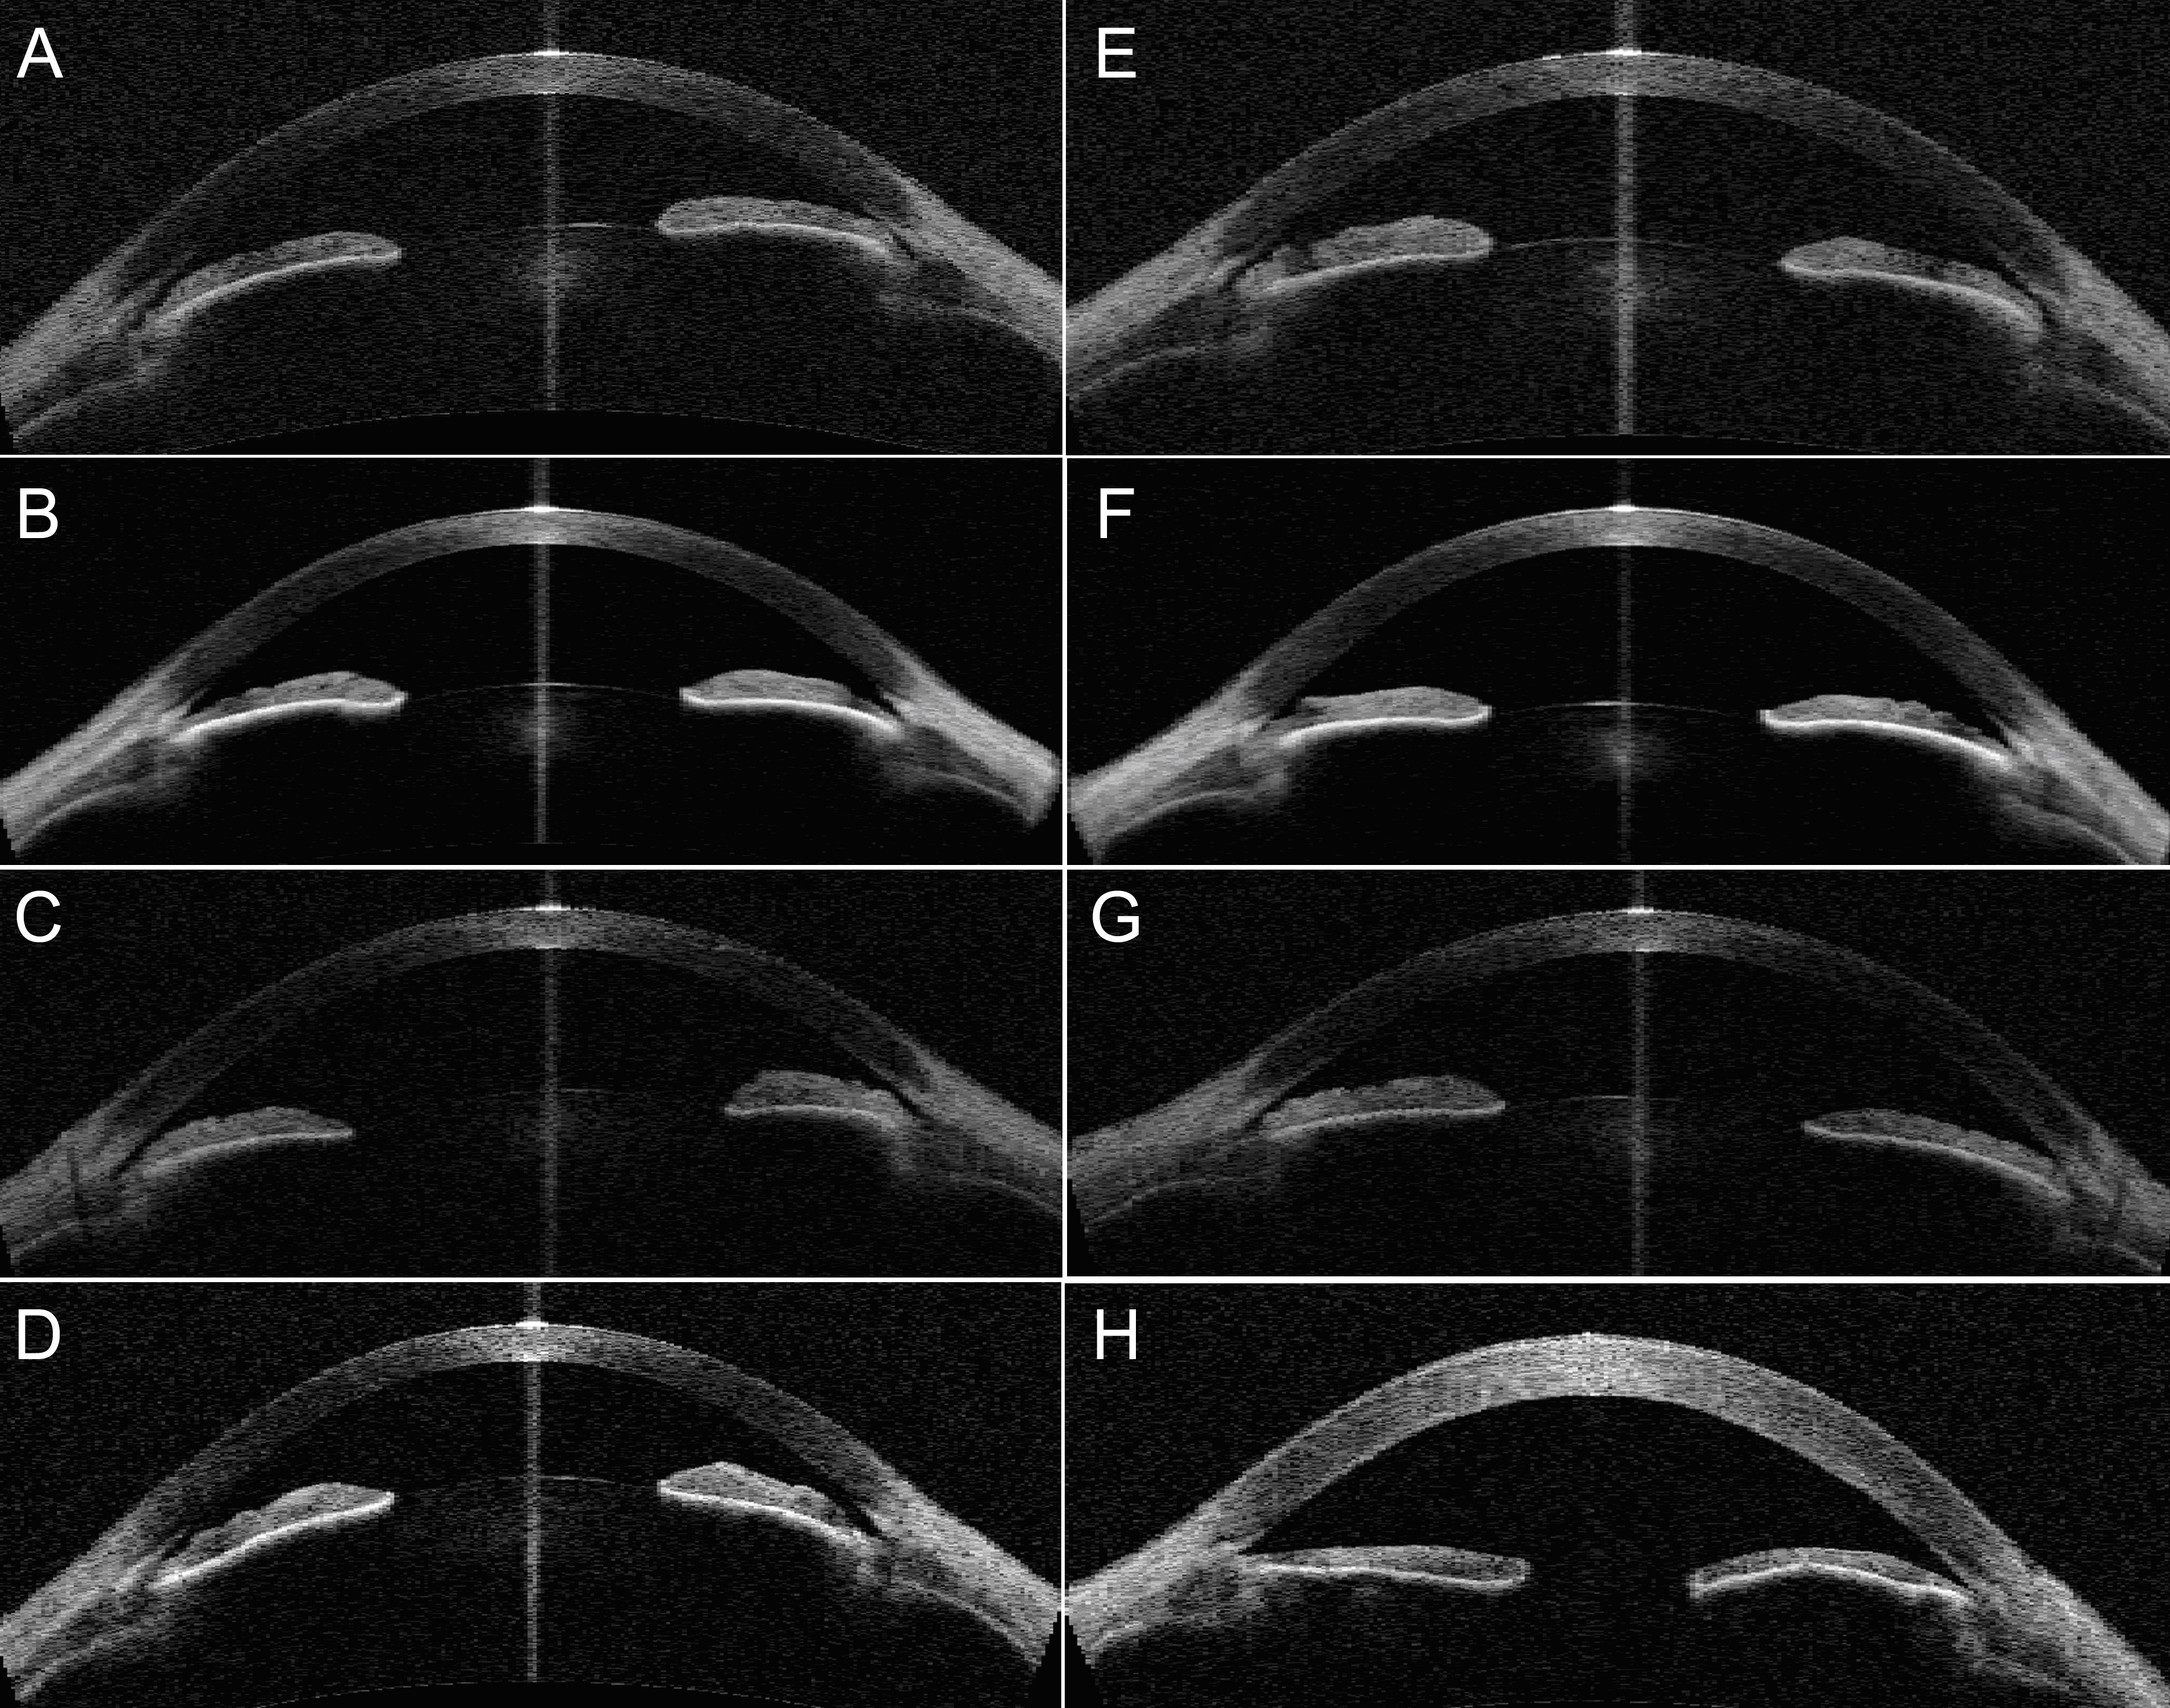

Figure 3. Anterior segment optical

coherence tomography findings for family 1. A-D:

Right eyes of individuals II:1 to II:4 respectively. E-H:

Left eyes of individuals II:1 to II:4 respectively. The

unaffected sister (II:2) shown in row 2 had closed angles on

anterior segment (AS)-OCT. Slit openings were observed for

individuals II:1 and II:3 on AS-OCT but their angles were closed

on gonioscopy. The proband shown in row 4 had the shallowest

anterior chamber depths. H: This shows a thickened

cornea from aphakia and corneal decompensation from previous

surgery in the proband.